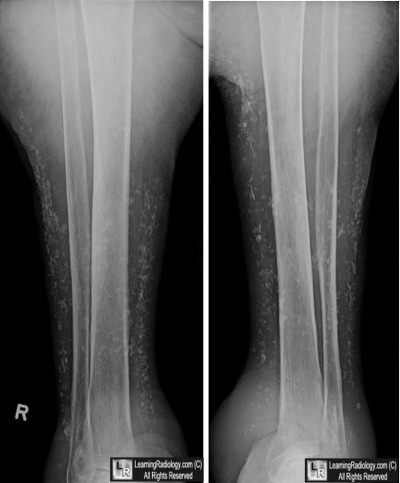

Frontal Radiographs of Both Legs

3. Chronic Venous Insufficiency

Chronic Venous Insufficiency